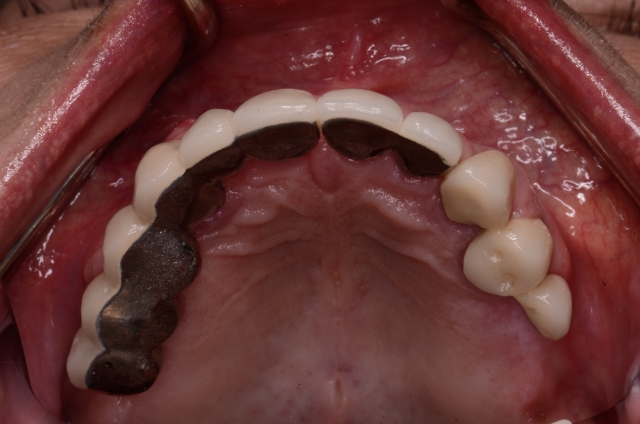

Photography is the linchpin of the entire co-discovery process. We take six pictures in every new case. Spear teaches that these are the six images that will improve case acceptance. Here’s an example:

Rampant root caries, extreme worn dentition and the corrosive effects of GERD are all effectively demonstrated with these photos. These photos get the ball rolling on patients requiring more comprehensive treatments due to a terminal dentition.